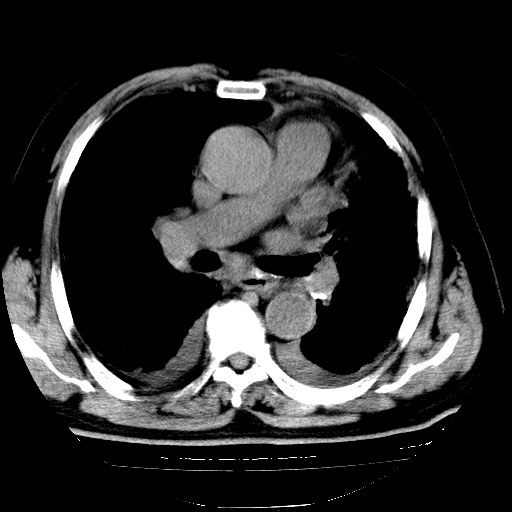

男,68岁,咳嗽、胸闷、发烧三天,查体:双肺散在湿罗音。

1.双肺间质纤维化并感染;

2.双肺慢支炎肺气肿;

3.支扩并感染;

4.肺原性心脏病;

5.双侧胸腔少量积液;双侧胸膜增厚。

慢性支气管炎伴感染、肺气肿;间质性病变;双侧胸腔积液。